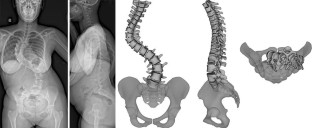

Adolescent idiopathic scoliosis treated with posteromedial translation: radiologic evaluation with a 3D low-dose system

Computed tomography can be used for three-dimensional (3D) evaluation of adolescent idiopathic scoliosis (AIS) patients, but at the expense of high radiation exposure, and with the limitation of being performed in the supine position. These drawbacks can now be avoided with low-dose stereoradiography, even in routine clinical use. The purpose of this study was to determine the 3D postoperative correction of AIS patients treated by posteromedial translation.

Forty-nine consecutive patients operated for AIS (Lenke 1–4) using posteromedial translation were included. Corrections were evaluated preoperatively, postoperatively and after at least 2 years using the EOS imaging system. 3D angles were measured in the plane of maximum deformity.

Mean number of levels fused and operative time were 13.5 ± 1 and 215 ± 25 min, respectively. Main thoracic, proximal thoracic, and lumbar curves corrections averaged 64.4 ± 18, 31 ± 10 and 69 ± 20 %, respectively. Mean T4–T12 kyphosis increased 18.8° ± 9° in the subgroup of hypokyphotic patients. Mean apical vertebral rotation reduction was 48.3 ± 20 %. Trunk height gain averaged 27.8 ± 14 mm. There was no pseudarthrosis or significant loss of correction in any plane during follow-up. Two patients (4 %) developed asymptomatic proximal junctional kyphosis, despite having normal thoracic kyphosis. Their sagittal balance was shifted posteriorly by 36 and 47 mm, respectively, by the operation, but revision surgery was not performed.

Low-dose stereoradiography provided 3D reconstructions of the fused and unfused spine in routine clinical use. Postoperative 3D analysis showed that posteromedial translation enhanced sagittal balance correction, without sacrificing frontal or axial correction of the deformity.

Fig. 3